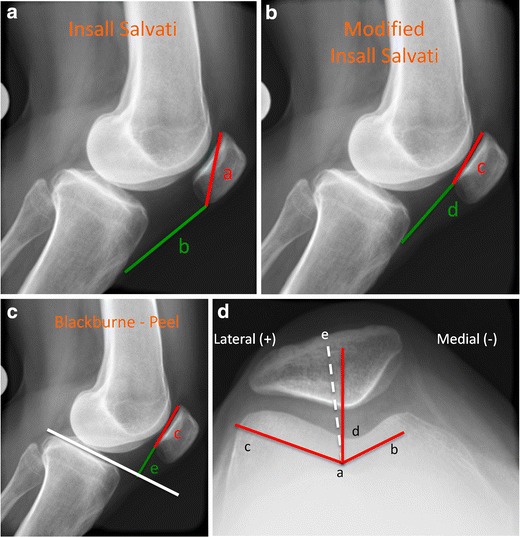

Patella alta or baja can be evaluated by a variety of methods of the lateral x-ray. The more common methods are the Insall-Salvati ratio and the Blackburne-Peel index. The Insall-Salvati ratio [20] compares the length of the patellar tendon with the patellar height. A normal ratio is 0.8–1.2 with patella alta occurring when the ratio of the length of the tendon to the patellar height is greater than 1.2 (Fig. 1a). A modified Insall-Salvati ratio can also be calculated to determine patellar height by using the length of the patellar articular surface instead of the entire patella (Fig. 1b). The Blackburne-Peel index [21••] is calculated on the lateral view with normal values between 0.5 and 1.1. This ratio is the length of the articular surface of the patella divided by the length of the patellar tendon from the lower pole of the patella to a line extending parallel to the tibial plateau (Fig. 1c). Several studies have evaluated the ease of use of the multiple methods of assessing patellar height. Berg [22] found that the Blackburne-Peel index was the most consistent at reproducing patellar height.

Fig. 1.

Patellofemoral radiographic measurement techniques. a Insall Salvati ratio is calculated by dividing patella length by the patellar tendon length (a/b). A normal ratio is between 0.8 and 1.2. b Modified Insall Salvati ratio is calculated by dividing the patellar articular surface length by the length of the patellar tendon (c/d). Mean normal is 1.25. c Blackburne-Peel ratio is calculated by dividing the patellar articular surface length by the length from the distal pole of the articular surface to a line extending from the tibial plateau (c/e). Normal is between 0.5 and 1.1. d The sulcus angle (b- > a- > c) helps assess femoral dysplasia. Normal is around 140°; dysplasia is indicated when the angle is larger. The congruence angle is measured between the bisector of the sulcus angle and the lowest point on the articular edge of the patella (e- > a- > d). The mean congruence angle is –6°. Medial is (–) and lateral is (+); lateral subluxation has a + angle

Patellar subluxation and trochlear dysplasia is evaluated on the axial view by measuring the congruence angle and the sulcus angle (Fig. 1d) [19••]. A different axial view, the Laurin view, taken with the knee flexed to 20°, allows better determination of lateral patellar tilt through measurement of the lateral facet angle (α angle) [23].